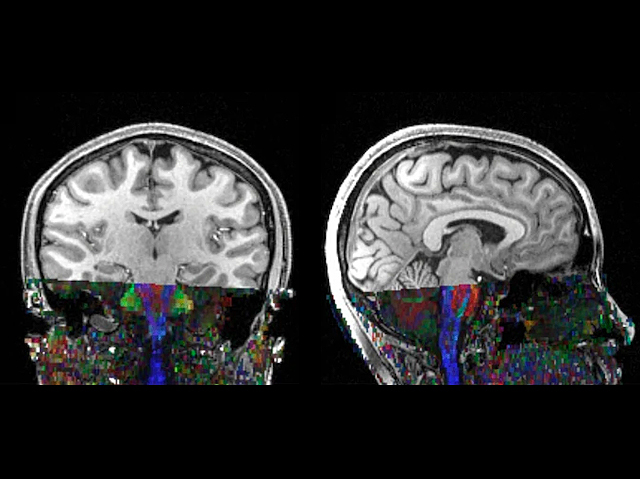

Recovering from Paralysis

Nerve affected by Bell's palsy – a rapid onset temporary facial paralysis of unknown cause – analysed by MRI reveals not axon damage but myelin sheath injury which can recover thus explaining why the disorder is usually self-limiting